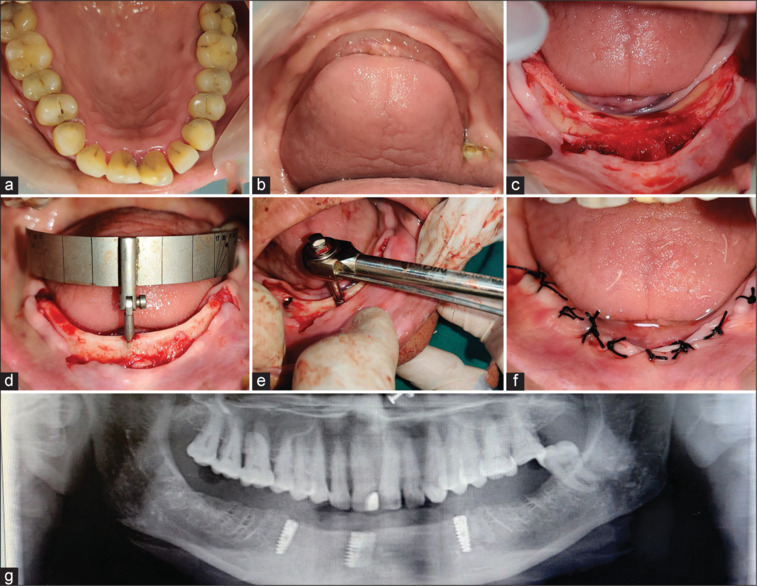

无牙患者残牙嵴的持续吸收给传统义齿修复带来了很大的挑战。传统义齿的固位和稳定性大打折扣,特别是当下颌嵴严重吸收时。使用种植牙对此类患者进行康复治疗已被证明是一种成功的治疗方式。有了明显的引导手术,可以实现准确和可预测的种植体放置。本病例系列描述了使用引导全上四技术和种植保留覆盖义齿修复吸收下颌弓的修复康复。

Continued residual ridge resorption in edentulous patients causes a great challenge in prosthetic rehabilitation by conventional denture. Retention and stability are greatly compromised in conventional dentures, especially if mandibular ridge is severely resorbed. Rehabilitation of such patients using dental implants has been proven as a successful treatment modality. With the evident of guided surgery, accurate and predictable implant placement can be achieved. This case series describes the prosthodontic rehabilitation of resorbed mandibular arches using guided all-on-four technique and implant retained overdentures.